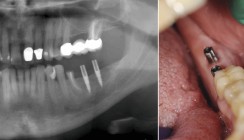

Die Patientin stellte sich mit einer Begleitperson zur Abklärung von Schmerzen in der Unterkieferfront bei ungenügendem Prothesenhalt im Unterkiefer vor. Es fand sich eine stegfixierte Unterkieferprothese auf drei in den späten 70er-Jahren des vorigen Jahrhunderts von extraoral Regio 32, 41, 42 eingebrachten TMI-Schraubenimplantaten nach BOSKER et al.4 Ein eigentliches Prothesenlager war bei der vorliegenden extremen Alveolarkammatrophie mit völligem Verlust des Vestibulums nicht mehr vorhanden. Klinisch war bei vorhandener Druckdolenz keine Lockerung der Stegkonstruktion festzustellen. Die Implantate 32 und 41 zeigten aber eine erhöhte Sondierungstiefe mit Blutung. Das Kauvermögen war stark eingeschränkt. Röntgenologisch lag eine periimplantäre Osteolyse bei 32 und 41 vor. Das Implantat 42 war dagegen unauffällig (Abb. 11). Nach Durchtrennung des Steges wurde die Lockerung der Implantate 32 und 41 offensichtlich, die Indikation zu deren Entfernung wurde gestellt.

Da ein ausreichender Prothesenhalt ohne Fixierung durch Implantate zukünftig nicht möglich gewesen wäre, andererseits sich konventionelle präprothetisch-chirurgische Eingriffe wie eine Vestibulumplastik oder eine Augmentation des atrophierten Alveolarkamms wegen der allgemeinmedizinischen Problematik verbaten, wurden in derselben Sitzung durchmesserreduzierte Titanschraubenimplantate (Straumann Roxolid RN 3,3 mm) Regio 31 und 33 (Abb. 14) minimalinvasiv („flapless“) inseriert. Dadurch konnte das Nachblutungsrisiko reduziert werden. Die vorhandene Prothese wurde ausgeschliffen, weichbleibend unterfüttert und als Verbandplatte eingegliedert, die Patientin wegen der allgemeinmedizinischen Problematik und der Antikoagulation kurzstationär aufgenommen.